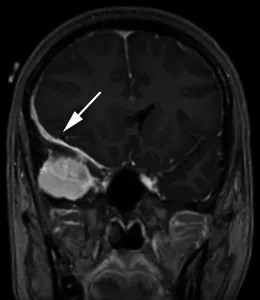

一名35歲頭痛女性的造影后冠狀T1加權(quán)序列顯示

一名35歲頭痛女性的造影后冠狀T1加權(quán)序列顯示,右中顱窩內(nèi)有均勻增強(qiáng)的軸外質(zhì)量,并有寬闊的硬腦膜尾(箭頭)沿著蝶骨翼延伸,并圍繞右額葉的側(cè)面。腫塊導(dǎo)致大腦鐮下向左突出7毫米,右側(cè)腦室消失。手術(shù)時(shí)的組織學(xué)結(jié)果為腦膜瘤(1級(jí))